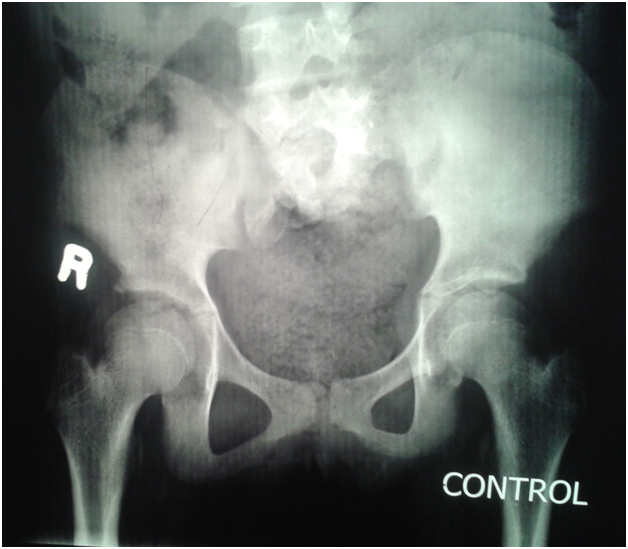

An eleven year old girl was presented to with chronic constipation, persistent dribbling of urine and recurrent urinary tract infections since early childhood. She received treatment by local physicians but remained without proper response. On examination, child was a febrile and her bladder was palpable. Her buttocks were flattened (Figure 1) and external genitalia were wet and excoriated. Anal tone was found decreased on digital rectal examination and the rectum was loaded with hard stool. No definite neurological deficit was found. She was catheterised and stool evacuated with per rectal enema. Her blood analysis showed low haemoglobin (8.1gm %), leucocytosis and raised serum creatinine level (2.2mg %). Urine analysis showed plenty of pus cells and growth of E. coli. Ultrasonography suggested bilateral hydro uretoronephrosis (rt>>lt) with loss of cortico medullary differentiation on right kidney and thickened irregular bladder with significant post void residual urine. Tc-99m DTPA renogram shows poorly functioning right kidney and satisfactorily functioning left kidney. Complete sacral agenesis, 5th lumbar vertebral atrophy and scoliosis with convexity towards right side seen in the control film (Figure 2) while neurogenic bladder with bilateral grade V vesico- ureteric reflux revealed on Voiding phase cystourethrogram (Figure 3). Child was further evaluated with urodynamic study, which suggested an overactive bladder in filling phase (Figure 4). Repeat blood analysis shows (Figure 4) normalisation of serum creatinine (1.2mg %). Her catheter has been removed and she has been placed on self clean intermittent catheterisation along with anti cholinergic (oxy butinine 5mg/daily) and laxative.

Figure 2 Complete Sacral agenesis, 5th lumbar vertebral atrophy.

Figure 3 Complete Sacral agenesis, 5th lumbar vertebral atrophy